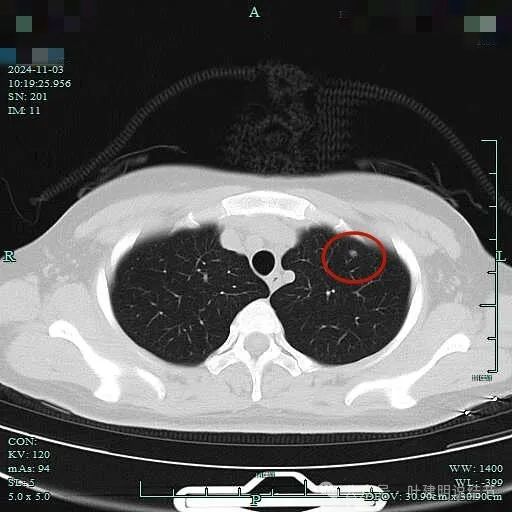

2、影像展示与分析:

非薄层平扫上病灶位于左上叶,仅约4-5毫米,磨玻璃密度,轮廓与边界清,实性成分不明显,但并不太淡。